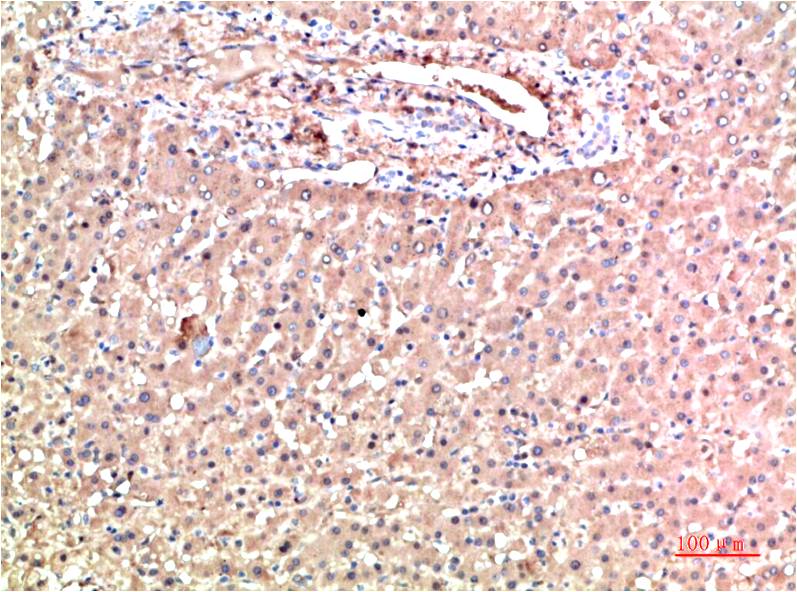

TTR Mouse Monoclonal Antibody(5G9)

Applications :WB, IHC

| Recommended dilutions: | WB 1:1,000-2,000 IHC 1:100-200 |

| Specificity: | The TTR Mouse Monoclonal Antibody can detects endogenous TTR proteins. |